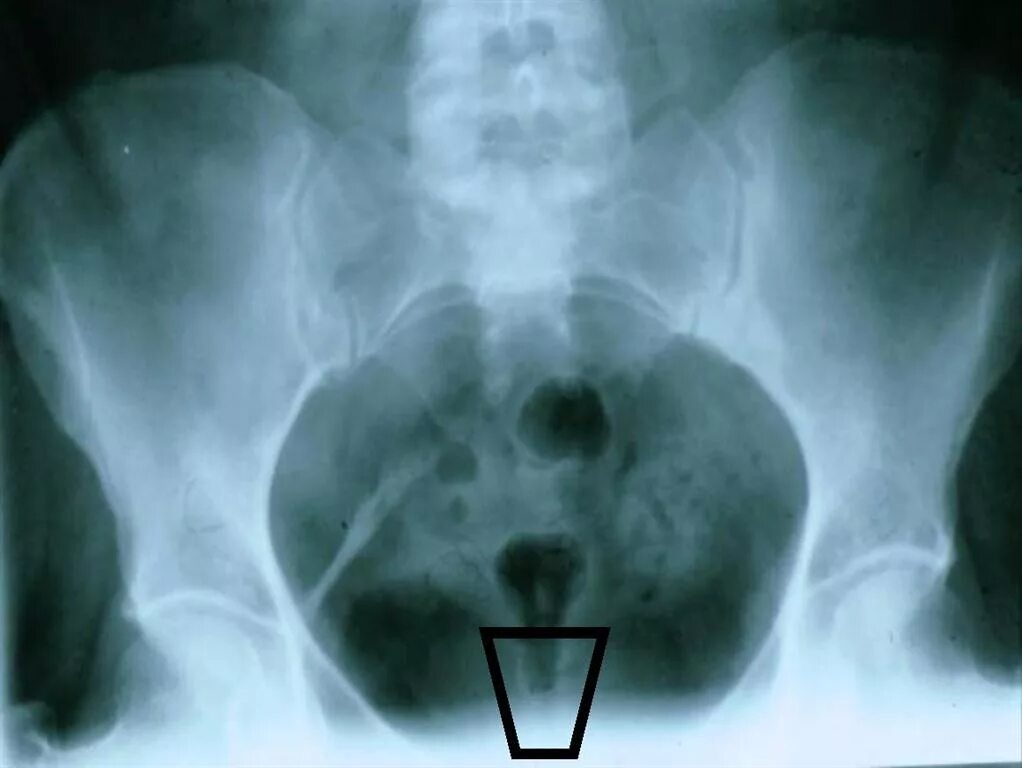

Снимок копчика